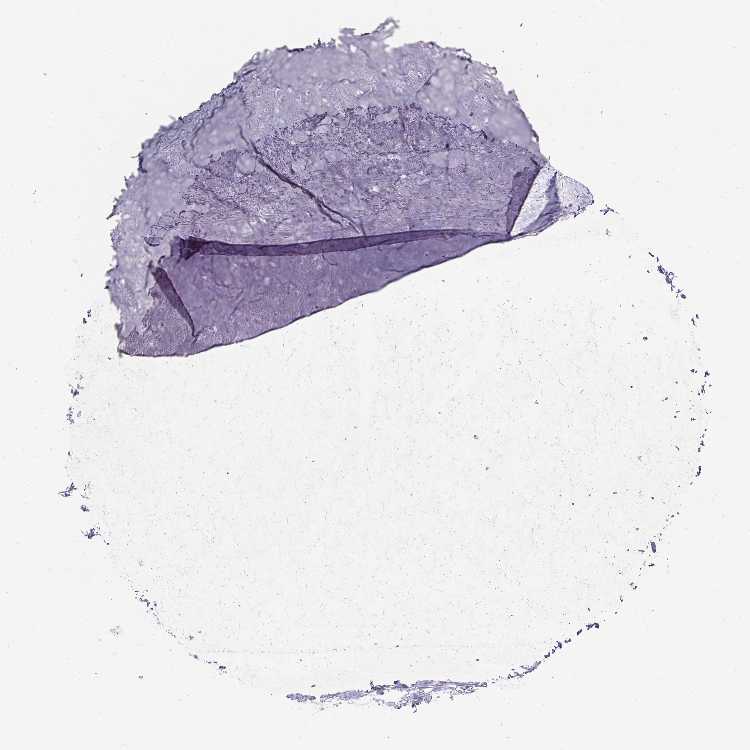

SOFT TISSUE 1 - Antibody stainingi

Antibody staining in the annotated cell types in the current human tissue is reported as not detected, low, medium, or high, based on conventional immunohistochemistry profiling in selected tissues. This score is based on the combination of the staining intensity and fraction of stained cells.

Each image is clickable and will lead to virtual microscopy that enables deeper exploration of all samples and also displays staining intensity scores, fraction scores and subcellular localization as well as patient and tissue information for each sample.

Antibody HPA016642Antibody HPA057112

Chondrocytes Not detectedNot detected

Fibroblasts Not detectedNot detected

Peripheral nerve Not detected-